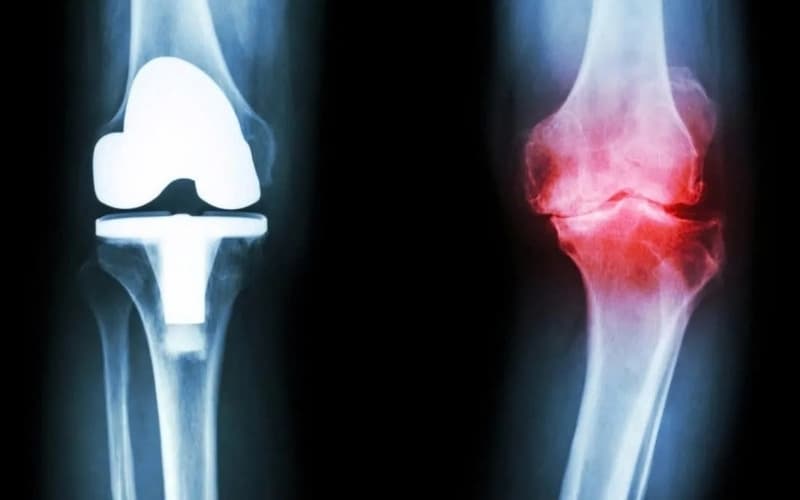

Thoái hóa khớp gối có châm cứu được không và những điều cần biết

Thoái hóa khớp gối là bệnh lý thường gặp ở người trung niên, cao tuổi hoặc người vận động quá tải, gây đau nhức, cứng khớp và đi lại khó khăn. Bên cạnh thuốc và phục hồi chức năng, nhiều người băn khoăn thoái hóa khớp gối có châm cứu được không, thoái hóa khớp gối có nên châm cứu không và hiệu quả thực tế ra sao.